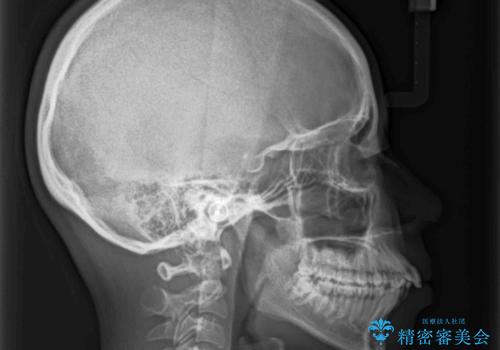

口元を積極的に引っ込めるために、上下左右の第一小臼歯を4本抜歯することとしました。

しっかりと通院するようになってからは順調に治療が進み、横顔の印象が変わるほどスッキリとした口元となりました。